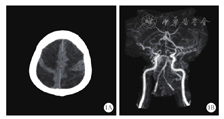

入院后静滴头孢曲松2 g、12 h 1次,万古霉素1 000 mg、8 h 1次,地塞米松12 mg、6 h 1次×3 d,并给予镇静、呼吸机辅助呼吸、脱水、抑酸、营养支持等综合治疗。弥散性血管内凝血(DIC)检测提示高凝状态,结合患者处于深度镇静,为防止下肢深静脉血栓形成加用低分子肝素抗凝,并给予阿司匹林抗血小板聚集治疗。入ICU后未再出现高热,3 d复查脑脊液仍培养出肺炎链球菌,但脑脊液常规生化指标明显好转;4 d脱机;6 d意识明显好转,格拉斯哥昏迷评分(GCS)15分,拔出气管导管;11 d转入神经内科进一步治疗,抗感染方案同前,地塞米松减至5 mg/d静滴,停用抗凝治疗;入院后12 d再次出现高热、谵妄,复查脑脊液提示细胞数、葡萄糖、微量蛋白均较前好转,但发热及谵妄症状逐渐加重至难以控制;14 d给予深度镇静并行气管插管后再次转入ICU,继续给予万古霉素抗感染,加用抗血小板聚集药物及营养支持等综合治疗;因凝血指标监测提示在正常范围内,未再加用抗凝治疗;16 d患者可完全脱机,镇静剂洗脱后患者意识恢复不理想,GCS评分8分,脑电双频指数(BIS)波动在60左右,NSE 23.04 μg/L、S100 1.040 μg/L,均明显增高,考虑存在神经系统损伤;18 d复查头颅CT示双侧大脑半球及脑干异常低密度影(图1A),头颅CT血管造影(CTA)示双侧大脑前动脉、中动脉及后动脉末梢血管显示不清,右侧大脑后动脉P1段未见显影,主要由后交通动脉代偿供血(图1B),拔管后患者咳痰能力差、舌根后坠;28 d行气管切开后彻底脱机,但患者四肢无自主活动,脑干功能保留,大脑高级皮质功能明显下降,格拉斯哥预后评分(GOS)2分,之后转入高压氧科继续康复治疗。

细菌性脑膜炎患者合并脑梗死的具体发病机制尚不明确,目前主流观点包括血管炎及颅内DIC学说。从20世纪30年代至60年代,脑膜炎患者颅内可见动脉及静脉炎性浸润[8,9,10,11],且临床脑血管造影发现该类患者存在脑血管局灶性狭窄[12,13],提示脑膜炎导致脑梗死可能与颅内血管炎有关。有研究表明,严重感染激活颅内凝血机制[14],而细菌性脑膜炎作为严重感染可激活颅内凝血过程;在脑膜炎患者脑脊液中存在凝血反应激活和纤维蛋白溶解抑制的情况,合并脑梗死患者尤为明显[15]。针对肺炎链球菌脑膜炎患者颅脑尸检的结果也显示,38%可见小血管炎症改变,未发现大动脉炎;但动、静脉栓塞的比例分别高达63%和56%,其中90%合并脑梗死[16],提示颅内DIC导致血管栓塞有可能是其发病机制。另外,炎症刺激导致血管痉挛及感染性心内膜炎脱落菌栓均是其可能的发病机制。该患者存在高凝状态,后期CTA检查提示颅内血管狭窄显示不清,推测肺炎链球菌脑膜炎合并脑梗死可能是颅内DIC和血管炎共同作用的结果,这也为病程中使用激素及抗凝治疗提供了理论依据。